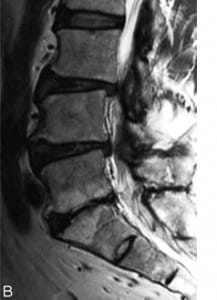

• modic

modic